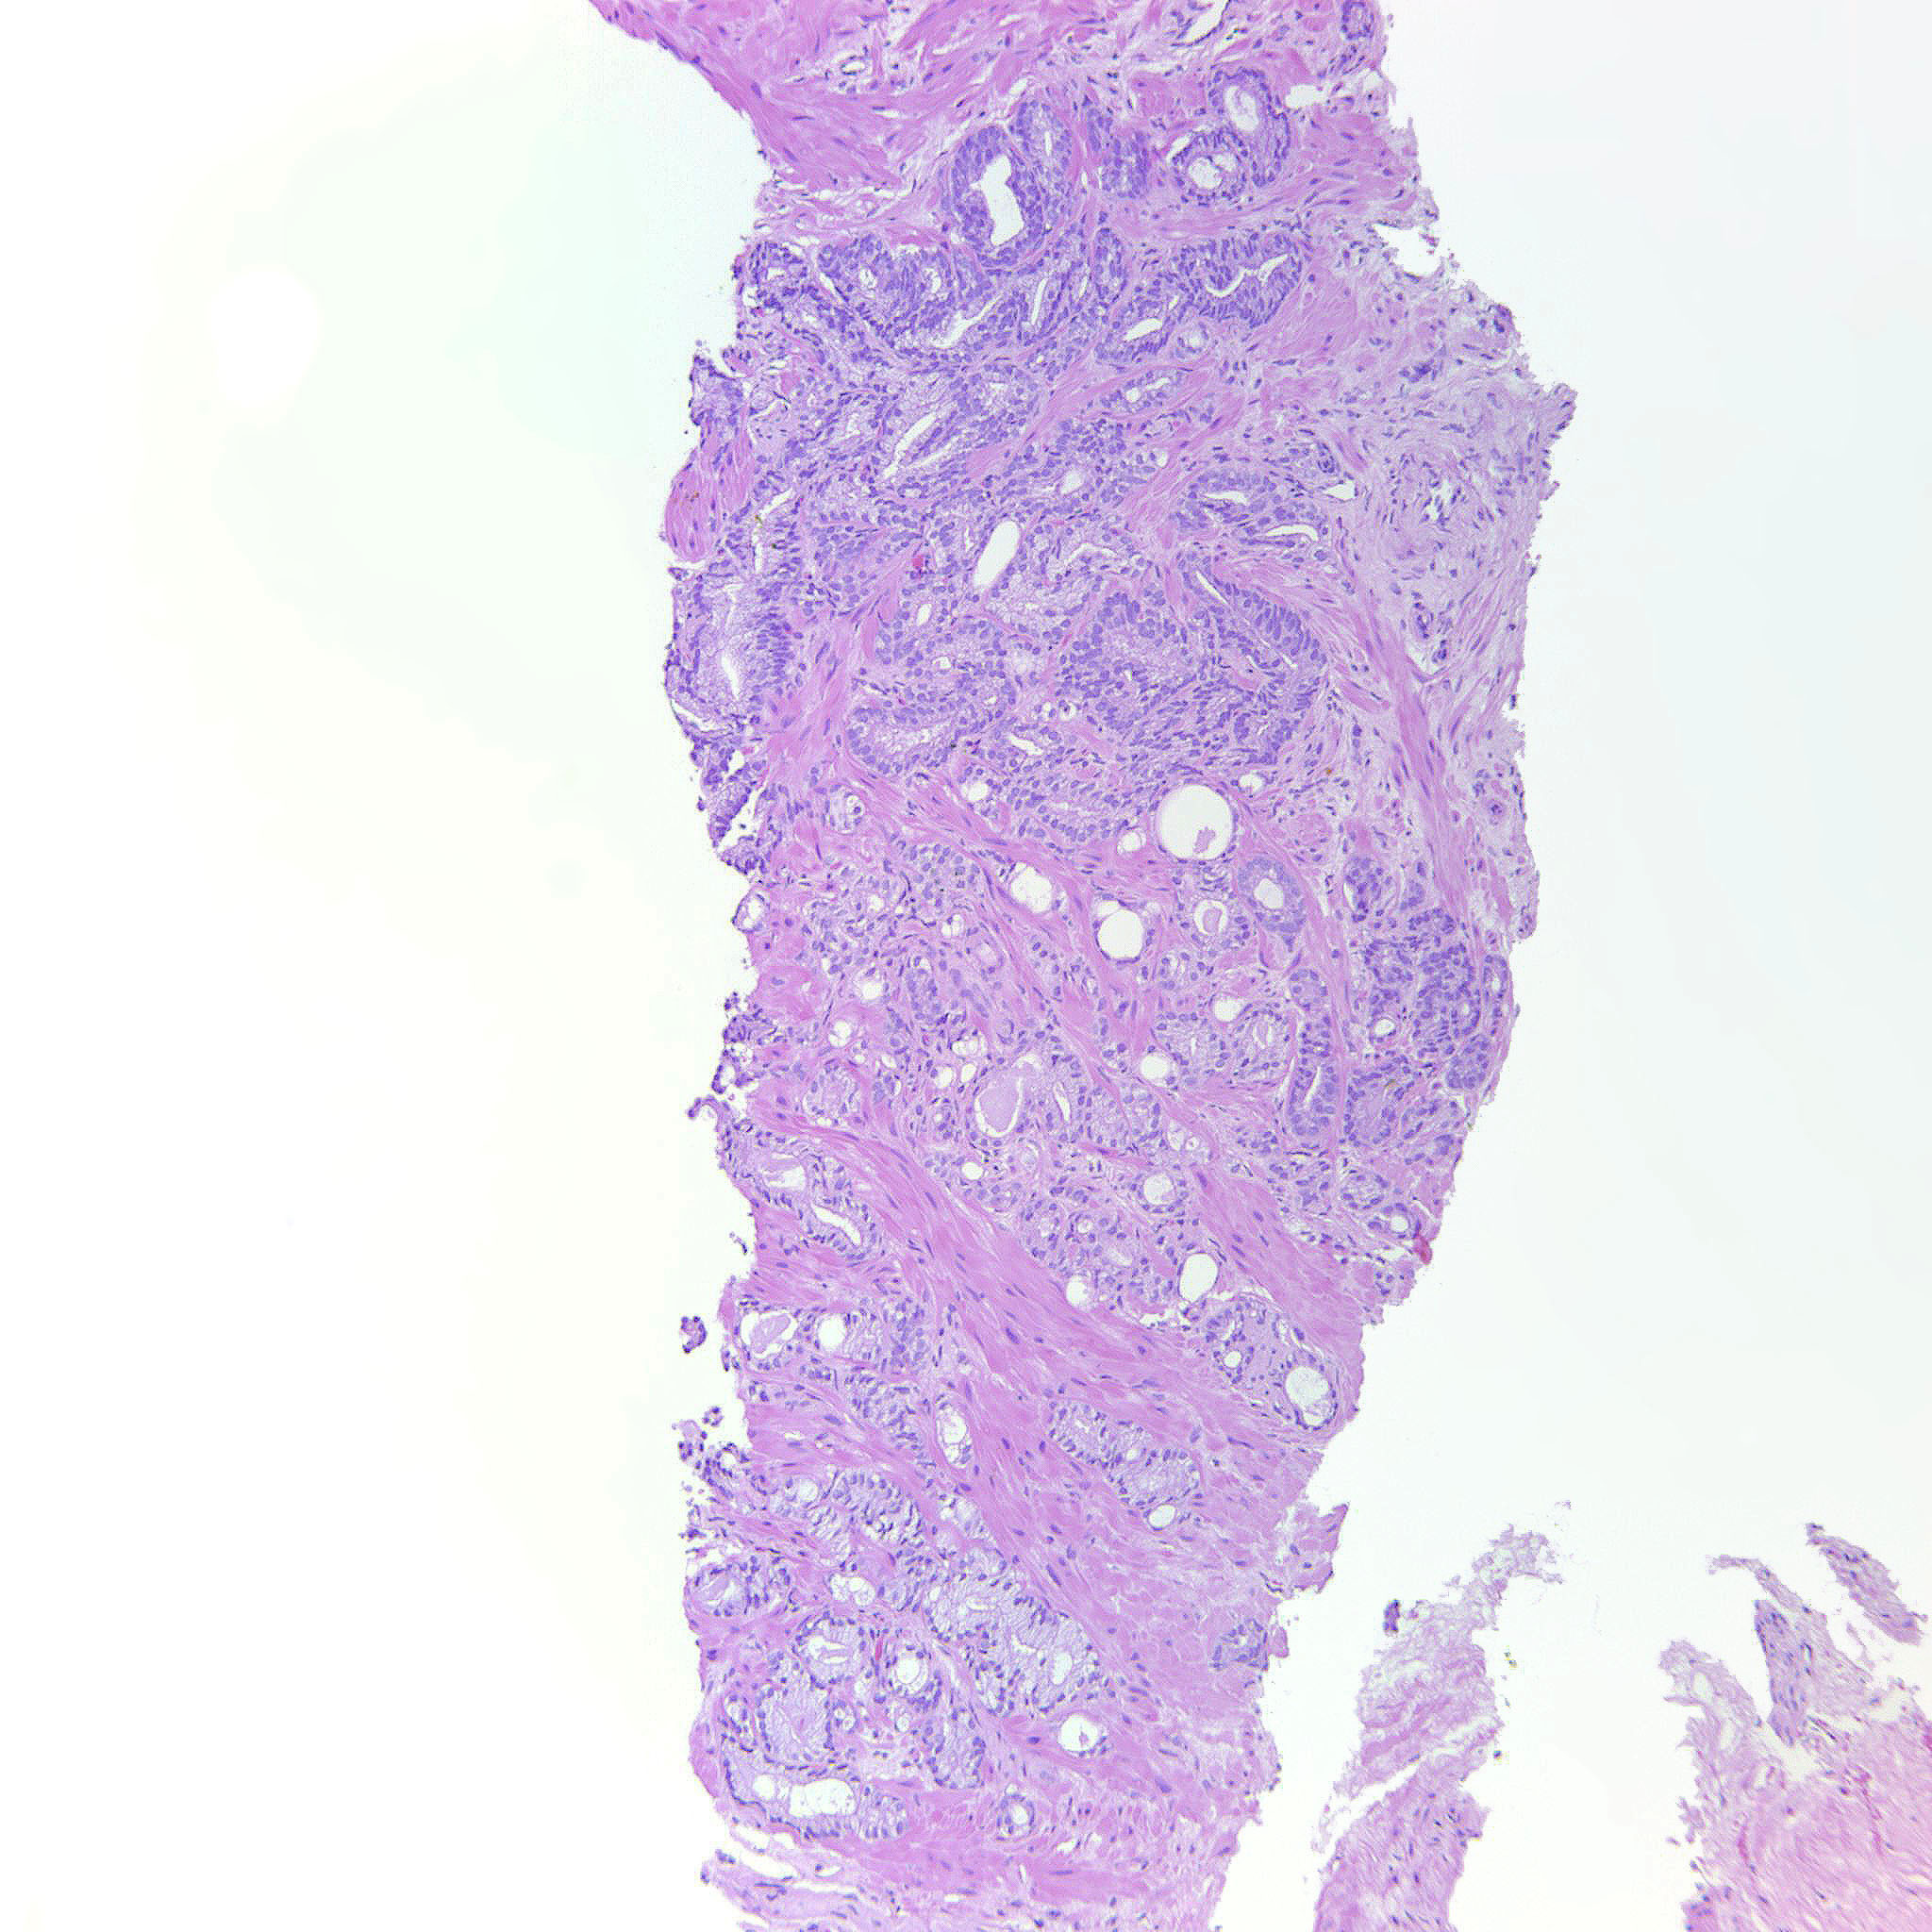

Consensus grade: GS 3+4=7 (ISUP 2)

Case description (by case creator):

Poorly formed and fused glands are seen.